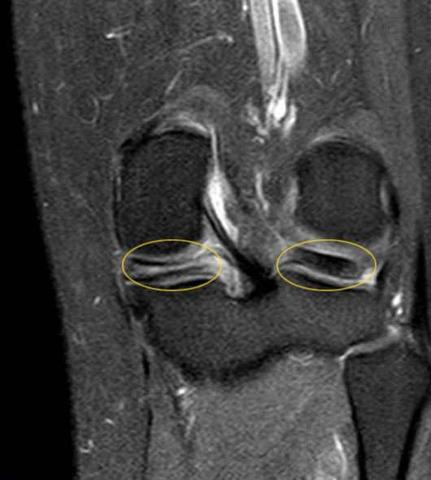

Ein Meniskusriss kann zu einer vorübergehenden Arbeitsunfähigkeit führen, da das betroffene Knie Zeit zur Heilung und Erholung benötigt. Die Dauer der Arbeitsunfähigkeit hängt von verschiedenen Faktoren ab, wie zum Beispiel der Art und Schwere des Risses, dem Alter des Patienten und der Art der beruflichen Tätigkeit.

Ein Meniskusriss kann in einigen Fällen konservativ, also ohne Operation, behandelt werden. Die Dauer der Genesung hängt von verschiedenen Faktoren ab, wie der Art und Größe des Risses sowie der individuellen Heilungsfähigkeit des Patienten.

Es ist wichtig zu beachten, dass nicht alle Meniskusrisse ohne Operation erfolgreich behandelt werden können. Wenn wiederholt Schmerzen auftreten oder sich Teile des Meniskus im Gelenkspalt befinden, ist eine Meniskusoperation empfohlen.